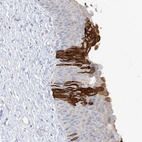

Immunohistochemical staining of human urinary bladder shows strong cytoplasmic positivity in urothelial cells.